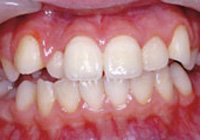

症例2:乱ぐい歯「歯並びが乱れている」

治療前 治療後